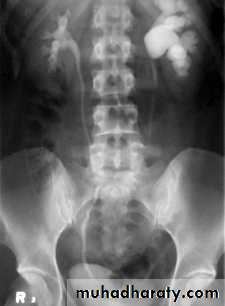

32- Stone

33- PUJ obstruction